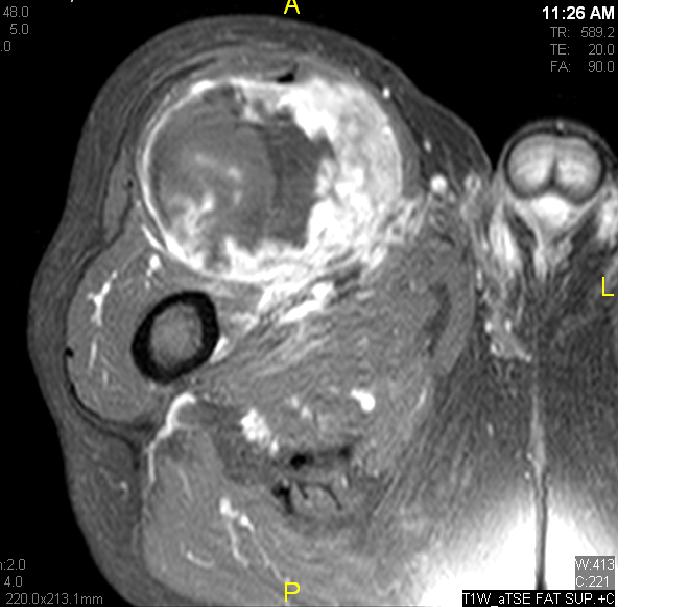

Fig. 11 – 13 Axial (Fig. 11), Coronal (Fig. 12) and Sagital (Fig. 13) contrasted T1-weighted MR images show a large heterogeneous mass with central and peripheral

enhancement. Multiple thick trabeculations. Central low signal intensity image is compatible with necrosis and hemorrhage.